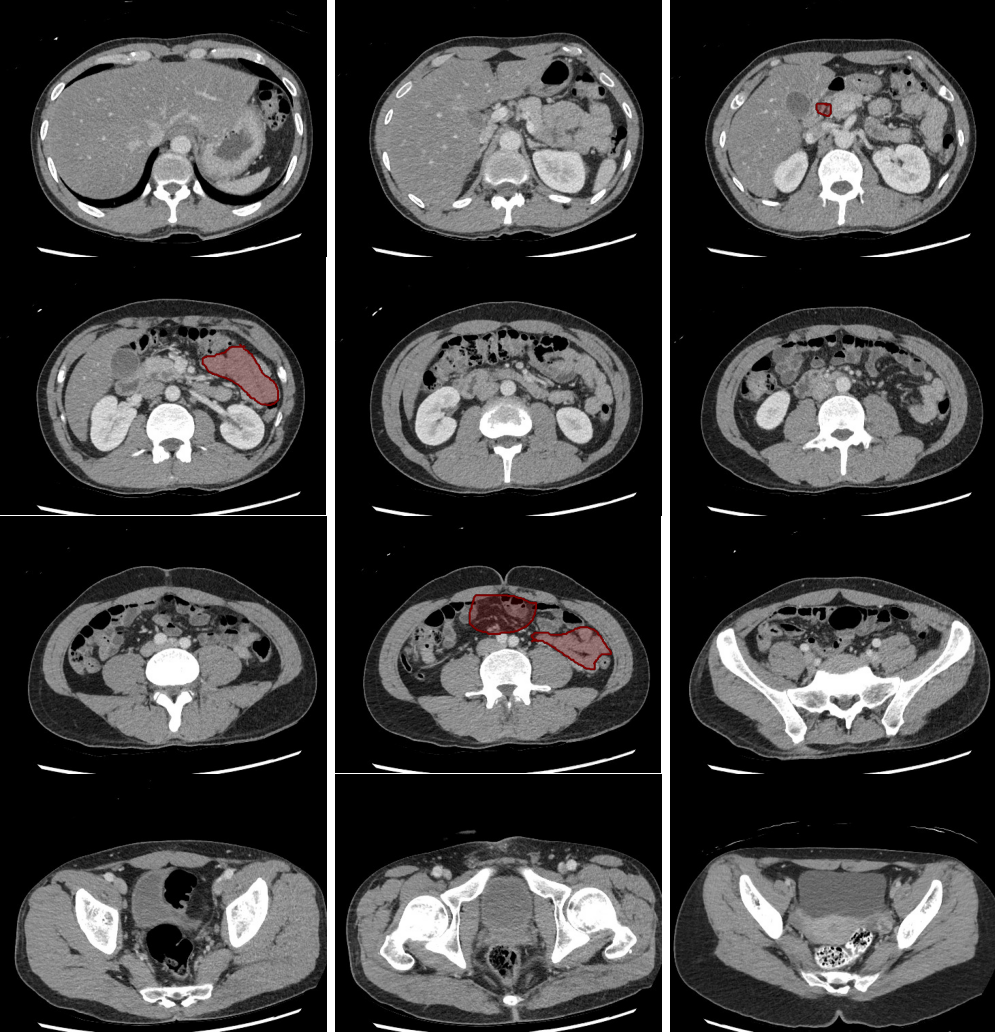

- Masses in the mesentery/peritoneum are often overlooked. Take advantage of multiplanar imaging and look in characteristic locations for peritoneal lesions.

Slice 1

Slice 2

Slice 3

Slice 4

Slice 5

Slice 6

Slice 7

Slice 8

Slice 9

Slice 10

Slice 11

Slice 12